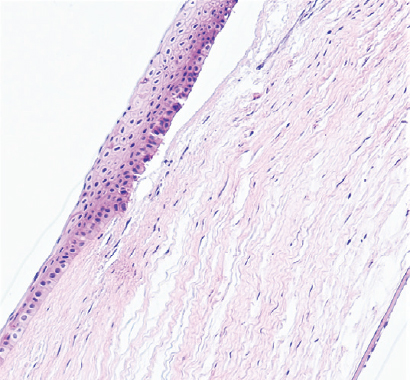

Режим 5. При данной мощности эпителий роговицы на всём протяжении имел обычное строение. Передние 10–15 % стромы в месте воздействия были незначительно разрыхлены. Десцеметова мембрана и энодотелий оставалась без изменений (рис. 3).

Рис. 3. Фрагмент роговицы после воздействия в подгруппе 1а. Фульгурация, режим 5. Окраска гематоксилином и эозином. Увеличение ×100

Fig. 3. Fragment of the cornea after exposure in subgroup 1a. Fulguration, mode 5. Stained with hematoxylin and eosin. Magnification ×100

На первом этапе эксперимента воздействие на роговицу в режиме 5 как клинически, так и гистологически выглядело недостаточным. Изменения охватывали лишь 10–15 % передней стромы. Учитывая, что в норме толщина роговицы кролика в центре составляет примерно 350 мкм, воздействию подвергались лишь около 50 мкм стромы. При воздействии в режиме 6 и 7 через 3 мес. изменения стромальной структуры распространялись примерно на 150 мкм. Воздействие в режиме 8, по нашему мнению, является избыточным. У кролика на этом режиме воздействия были самые грубые изменения в строме. Кроме того, в патологический процесс вовлекалась десцеметова мембрана.